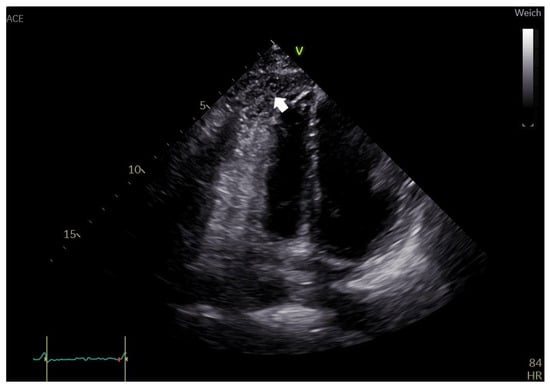

2. Case Report